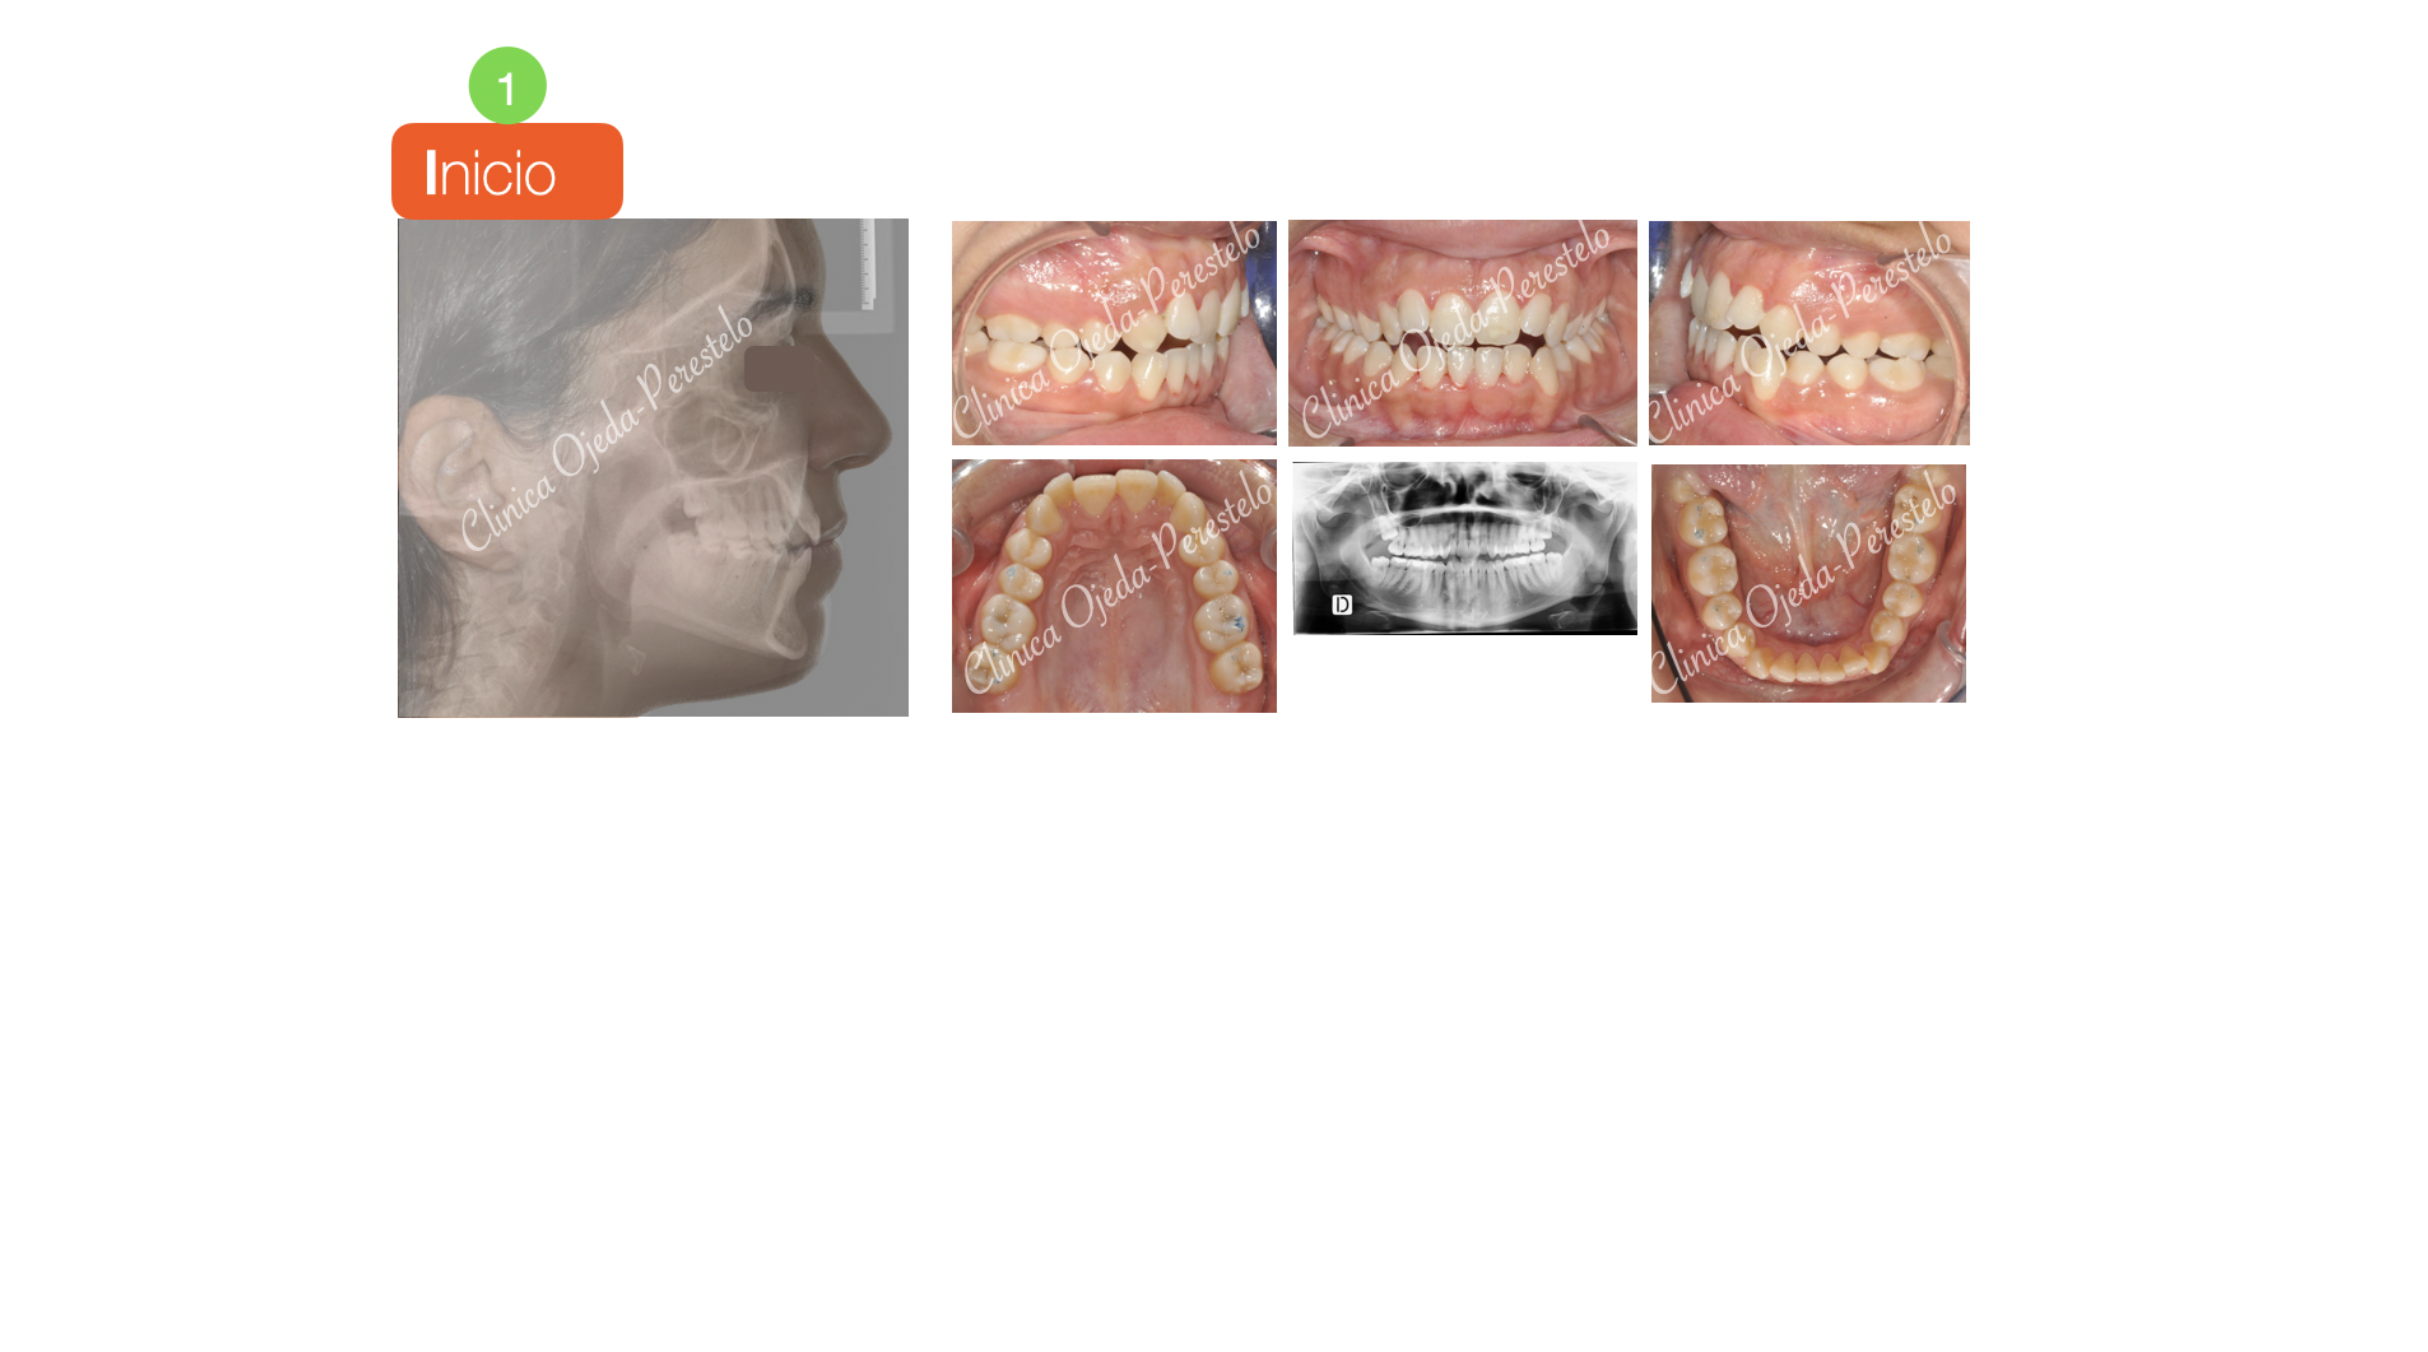

Clase II con Mordida Abierta

Presentamos este caso con apiñamiento  y mordida abierta tratado con alineadores y con extracción de los cordales .